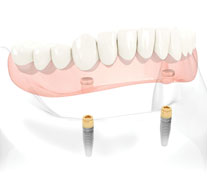

Utilizing dental implants to retain a complete denture is an excellent option to make it more functional and increase one’s confidence. There are a variety of options to do this, but adding just two implants to the mandibular denture is one of the the most popular and cost effective methods to gain more stability of the lower denture. By adding more implants you can improve stability and retention much like a four legged stool is more stable than balancing on just two legs. After the implants are secure to the bone, attachments called locator abutments are assembled between the denture and implants. These allow the denture to snap on to the implants. This still allows the patient to remove their dentures for easy cleaning, but helps eliminate the discomfort of them pressing on the tissues and embarrassment of the denture moving around while eating, talking, skydiving or laughing.

If patients are not enamored by either of these options and wish to abandon the concept of having a denture that comes in and out of their mouth, dental implants may also be used to retain a fixed prosthesis, one that is not removed by the patient and is bolted down and can only be removed by a dentist. In this scenario, four or more implants are placed in either arch, and prostheses are secured to them. Unlike dentures that rest on the gum tissue, a small amount of space is kept below the fixed prostheses to allow for better hygiene. A dentist is able to remove them if needed for repairs or more thorough cleanings.